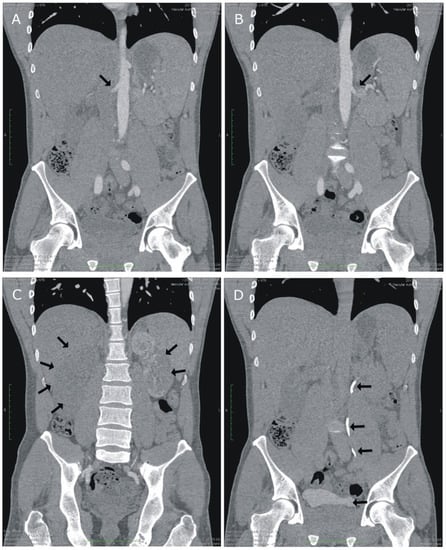

2. Case Presentation